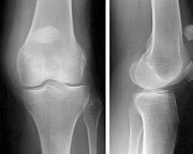

La articulación de la rodilla está formada por las partes inferior del fémur, superior de la tibia y posterior de la rótula actuando como una gran bisagra. Es la articulación más lesionada en el deportista y su tratamiento exige un gran conocimiento de la anatomía así como de la cirugía traumatológica, protésica y artroscópica.

Fracturas del tercio superior de la tibia

Las fracturas en el tercio superior de la tibia suponen el 1% de todas las fracturas y el 8% de las fracturas del anciano. Están causadas por fuerzas violentas que producen desviaciones laterales sobre la rodilla. La osteoporosis en el paciente de edad facilita estas fracturas. Son lesiones que también vemos en el ámbito deportivo fundamentalmente en aquellos deportes que exigen un sobreesfuerzo de la articulación de la rodilla como el esquí, el fútbol o el patinaje. En los deportistas suelen acompañarse, además, de lesiones ligamentosas que pueden pasar desapercibidas si no se realiza una exploración exhaustiva.

El tratamiento de las fracturas del tercio superior de tibia es quirúrgico con la finalidad de devolver a la rodilla su anatomía normal para el rápido inicio de la movilidad articular. Los avances en técnica artroscópica y los nuevos implantes permiten el tratamiento de estas fracturas de una forma poco agresiva y fiable que disminuye las complicaciones postoperatorias y agiliza el tiempo de recuperación.